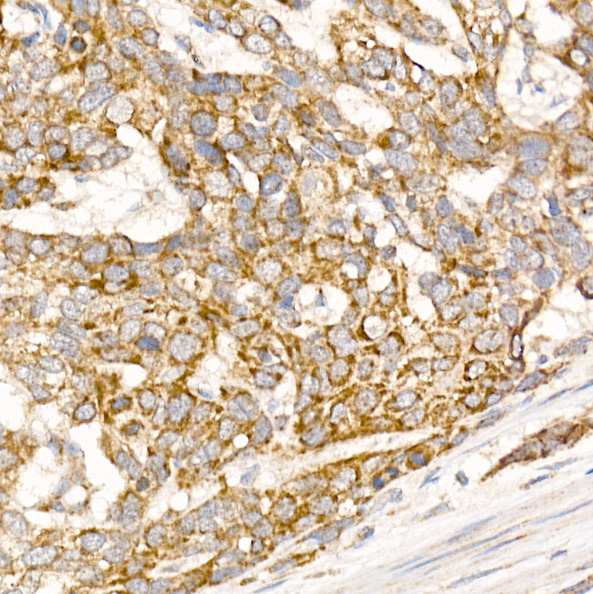

Immunohistochemistry of paraffin-embedded human esophageal cancer using Glycerol kinase Rabbit pAb at dilution of 1:150 .Perform high pressure antigen retrieval with 10 mM citrate buffer pH 6.0 before commencing with IHC staining protocol.

Immunohistochemistry of paraffin-embedded human liver using Glycerol kinase Rabbit pAb at dilution of 1:150 .Perform high pressure antigen retrieval with 10 mM citrate buffer pH 6.0 before commencing with IHC staining protocol.